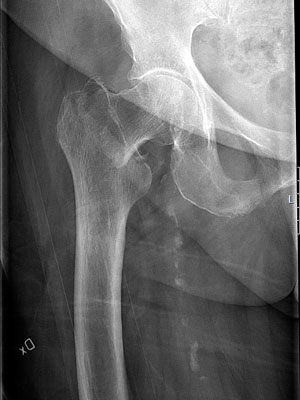

Med röntgenundersökning kan man också upptäcka icke-läkning och avaskulär caputnekros. Cirka 10 procent av de spikade/skruvade odislokerade cervikala frakturerna reopereras av ovanstående orsaker [24].

Höftproteser kan lossna eller slitas ned, varför patienter med höftprotes som upplever nytillkommen smärta också bör genomgå ny röntgenundersökning. Protesinfektion eller symtom på protesinfektion kan uppstå även långt efter primäroperationen. Protesinfektioner kan ge smärta som enda symtom. Blodprovtagning med infektionsparametrar bör ingå i undersökning av patienter med protes och nytillkommen smärta från sin proteshöft.

Cervikal höftfraktur hos 69-årig patient som halkat, opererad med skruvar. 2 år senare sökte han primärvården med smärta i höftleden. Röntgen visade caputnekros och skruvpenetration. Patienten remitterades till ortopedklinik och planerades för reoperation med extraktion av skruvar samt helprotes.

Haveri av osteosyntesmaterial. Till vänster: Patient med en initialt odislokerad cervikal höftfraktur. Patienten besvärades sedan operationen av värk i ljumsken och lateralt kring höften. Värken blev så pass uttalad att den störde nattsömnen. På slätröntgen sågs icke-läkning i frakturen, och den kaudala skruven hade backat och stack ut i mjukdelarna. Till höger: Patient med subtrokantär femurfraktur som opererats med lång märgspik. Patienten hade smärta och stelhet i höften och värk i framför allt ljumsken. Initialt var patienten nöjd med sin höft men hade fått mer och mer ont de senaste månaderna och hade svårt att promenera till närmaste affären. Osteosyntesmaterialet hade migrerat kraniellt, och kollumskruven hade skurit ut genom caput och penetrerade leden.